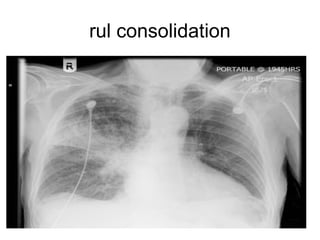

• RUL consolidationConfined

by horizontal fissure inferiorly and upper

half of oblique fissure posteriorly ,may

obscue right upper mediastinum

rul consolidation